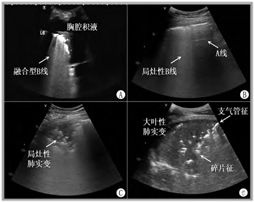

小儿肺超声通过高频探头捕捉肺部影像,无需造影剂、无需患儿憋尿或镇静,几分钟即可快速完成检查。它能清楚识别肺炎、肺水肿、肺实变、胸腔积液、气胸等常见肺部病变。